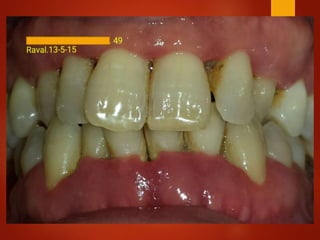

El documento es un registro médico odontológico que muestra las fechas de las visitas de un paciente al centro de salud El Raval, incluyendo exámenes y tratamientos realizados como la extracción de cálculos salivales en abril y mayo de 2012.